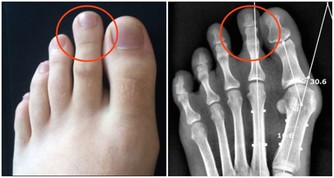

男性乳腺癌占總發病率1%。當發現乳房腫塊,尤其是質地較硬,邊界不清,表面不光滑,活動度差的腫塊,乳房皮膚局部凹陷或呈「橘皮狀」,乳頭內陷,或伴有乳頭溢血,以及腋窩淋巴結腫大的情況時,需馬上就診。